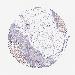

CANCER BREAST CANCER Show tissue menu

BRCA TCGA BRCA VALIDATION PROTEIN EXPRESSION

ANTIBODIES

AND

VALIDATION